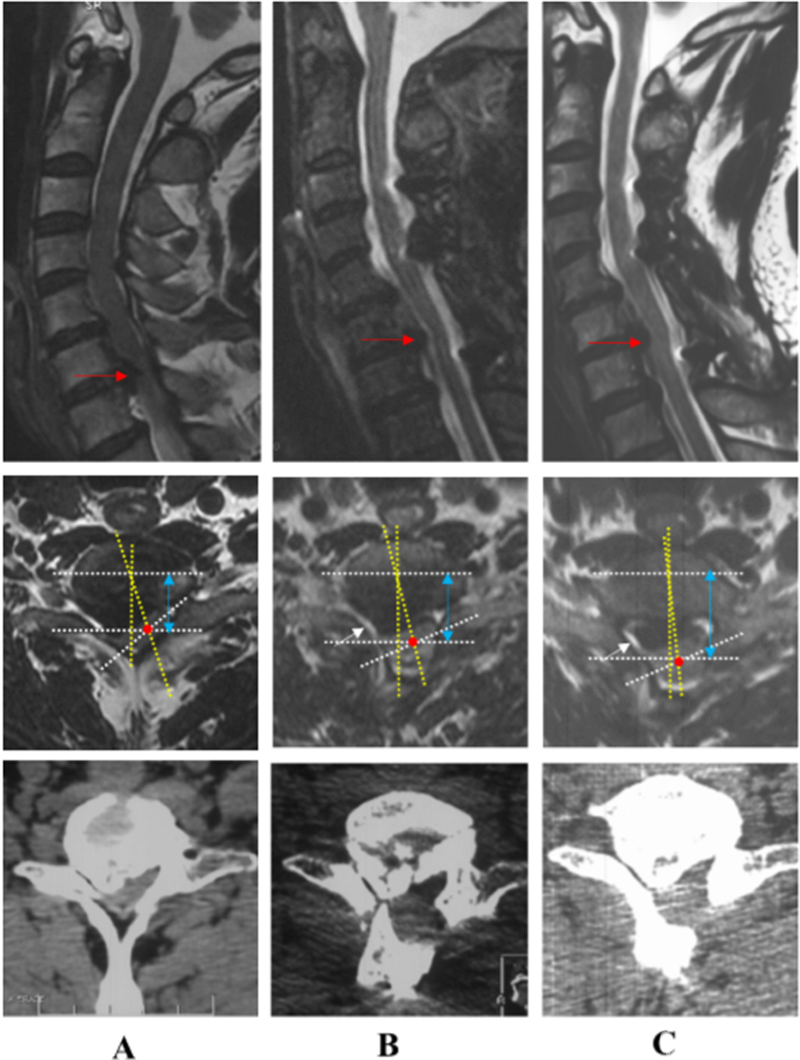

典型病例:刘某,女性,69岁,因“四肢麻木、疼痛,伴行走不稳、排尿无力1年,加重1月”,保守治疗无效。术前MRI显示C2 – C7脊髓明显受压,脊髓曲度变直,脑脊液带消失,C2-C7后纵韧带骨化,术前脊髓旋转和偏移角分别为36.3°和14.2°术前JOA评分为9。

在海军军医大学附属长征医院行ACAF治疗(手术节段C2-C7),脊髓减压彻底,脊髓旋转和偏移角显著变小。末次随访时,脑脊液、脊髓面积恢复良好,脊髓旋转和偏移几乎接近0°,由于脊髓横截面面积和位置恢复,脊髓中心前移1mm,恢复原位,JOA评分提高到15分,改善率为75%。脊髓减压彻底,神经功能改善优异,且未发生颈5神经根麻痹。

病例二

患者男性,46岁,主诉“双上肢麻木、无力、疼痛5年,加重1月”术前MRI显示C5-C7脊髓受压,骨化物压迫平面的脊髓旋转和偏移角分别为39.6°和17.4°。

在海军军医大学附属长征医院行C3-C7节段椎管成形术,脊髓间接减压但不完全,脊髓旋转和偏移角分别变为23.5°和13.6°,且术后出现右上肢不能上抬(C5神经根麻痹),原因可能是C4/5水平的右侧神经根由于偏右侧型骨化物压迫受到牵拉,加上脊髓向后漂移,麻痹侧神经根可能受到更大的张力。末次随访时,脑脊液、脊髓面积仍恢复较差,脊髓旋转和偏移角仍较大,脊髓向后漂移3.0mm,JOA评分由术前9改善到12,改善率为37.5%,仍残留部分麻木疼痛症状。